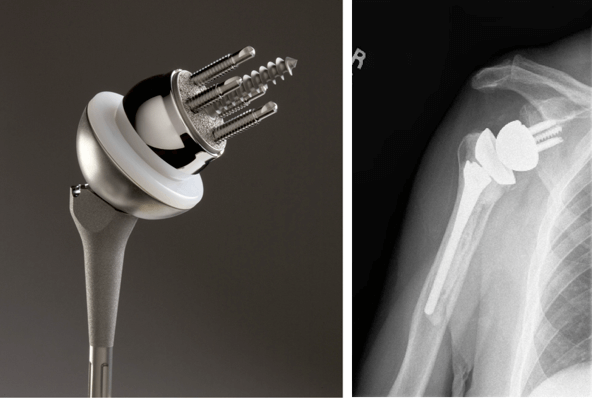

Имплантаты на ножке по своему строению могут быть анатомическими и обратными. Анатомический состоит из трех частей: головка, ножка и впадина. Назван так, поскольку полностью повторяет структуру человеческого плеча и по биомеханике, и по форме.

Установка такого протеза возможна только в том случае, если вращательная манжета не повреждена. При замене используется продукция таких мировых производителей как DePuy, Zimmer, Smith&Nephew, Biomet, Aesculap — B. Braun.

Обратный или реверсивный используется, когда вращательная манжета не функционирует и нарушена стабильность. Тогда головка крепится к суставной впадине (гленоидальному компоненту), а вогнутый имплантат впадины на ножке фиксируется на плечевой кости.

Для однополюсного эндопротезирования используются гемипротезы, то есть заменяющие только одну часть сустава. По способу установки делятся на поверхностные и штыревые (внедряются в кость).

Также имплантаты могут быть цельными или сборными (модульными). Модульные позволяют за счет подбора различных размеров элементов корректировать при необходимости положение плеча. Существуют следующие способы крепления протезов к кости: